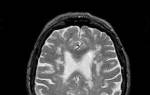

- Магнитно-резонансная томография – анализирует процессы на клеточном уровне;

Врачи подчеркивают, что резидуальная энцефалопатия представляет собой сложное состояние, требующее комплексного подхода к диагностике и лечению. Основными причинами этого заболевания могут быть травмы головы, инфекции, а также недостаток кислорода в мозге. Для диагностики специалисты используют нейровизуализационные методы, такие как МРТ и КТ, которые помогают выявить изменения в мозговой ткани.